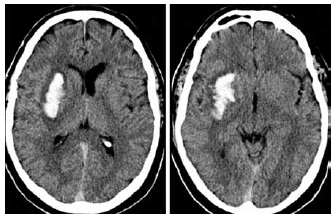

Considere a tomografia sem contraste apresentada a seguir.

O diagnóstico mais provável é